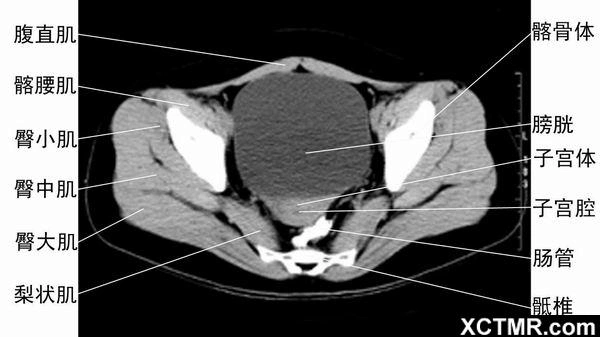

"腹部ct"精美解剖图(下)转载"华夏影像诊断中心"需要 - 抖音

点滴积累,成就影像专家.腹部ct断面解剖

腹部盆腔ct断层 microsoft word 文档